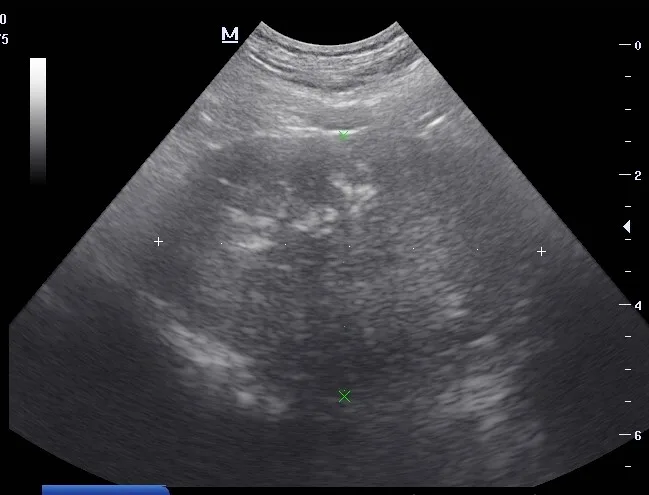

CBC and serum chemistry profile results were within normal limits, except for mildly elevated ALP (220 U/L; reference interval, 2-150 U/L). Transabdominal ultrasound showed an enlarged, heteroechoic prostate with multiple anechoic and hyperechoic foci, indicating a diagnosis of prostatitis (Figure).

Ultrasound images of the left (A) and right (B) prostate lobes. The prostate was enlarged and heteroechoic with multiple anechoic and hyperechoic foci.